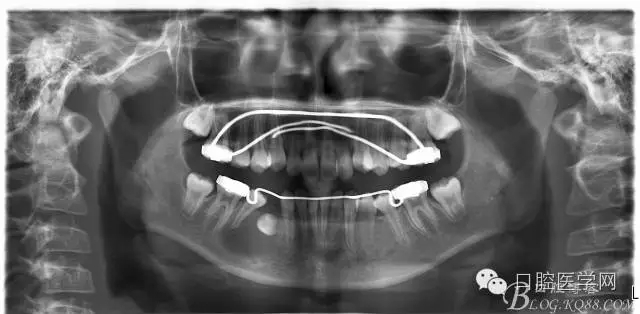

術(shù)后一個月 三個月 五個月 八個月 拔除第一雙尖牙后 曲斷片:

正畸查:替牙合。第一恒磨牙中性合。上牙弓尖圓型下牙弓方圓型。前牙覆合3度覆蓋7.5mm。下前牙咬到上舌側(cè)牙齦。上頜擁擠4.0mm,下頜擁擠

3.0mm。上頜稍前突下頜后縮,上下唇前突,上前牙覆蓋下唇,下唇外翻。面下三分之一過短,頦唇溝明顯,開唇露齒,頦饜窩明顯。顳下頜關(guān)節(jié)開閉口無彈響,無壓痛,開口型開口度正常。